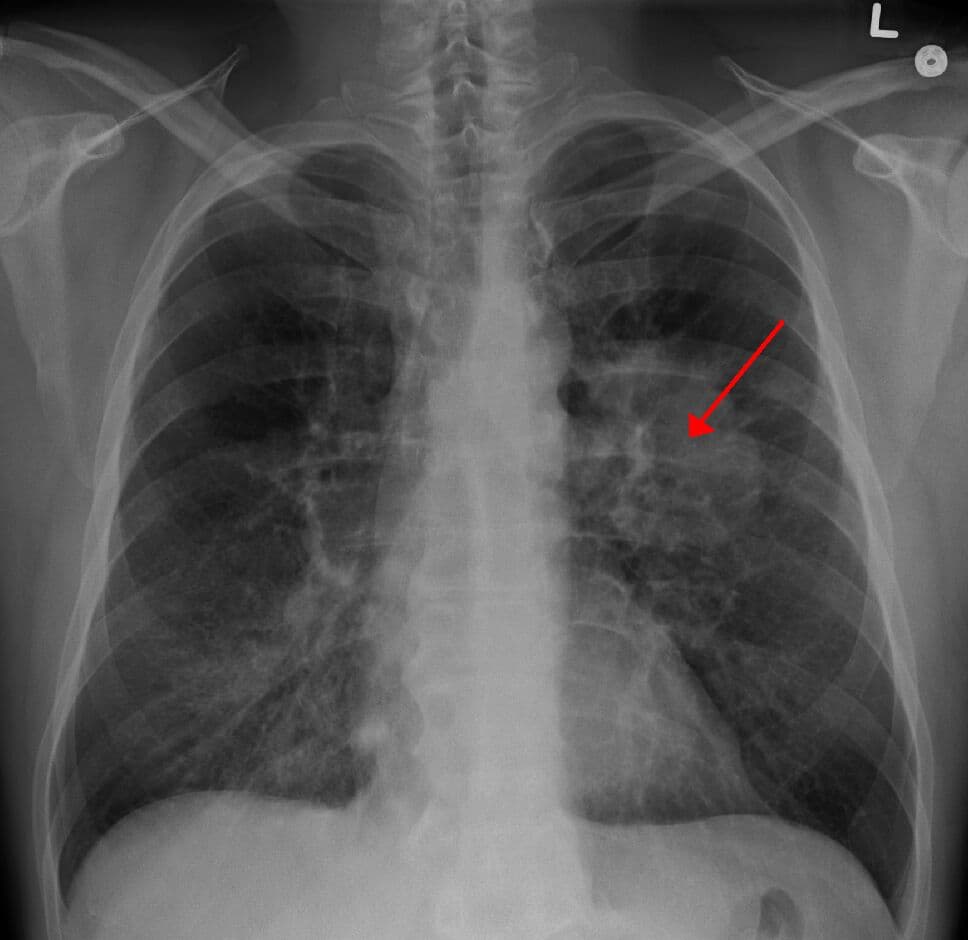

GAM MitoCan repurposes the investigational drug gamitrinib TPP hexafluorophosphate as a targeted IV therapy for non-small-cell lung cancer (NSCLC). Patients are prescreened for mitochondrial dysfunction through minimally invasive biopsies and blood tests to identify likely responders. As a mitocan therapy, GAM MitoCan selectively disrupts tumour cell mitochondria while sparing healthy tissue. Early use is expected to help patients who do not benefit from immunotherapy, offering a precision option to reduce tumour burden, minimise toxicity, and improve outcomes